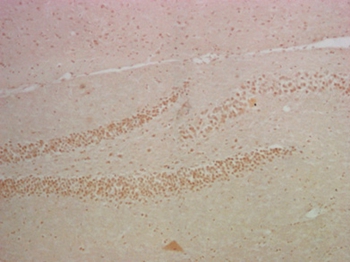

图片:

IHC staining of mouse hippocampus tissue with NFκB p65 mouse mAb(14H2) diluted at 1:200.